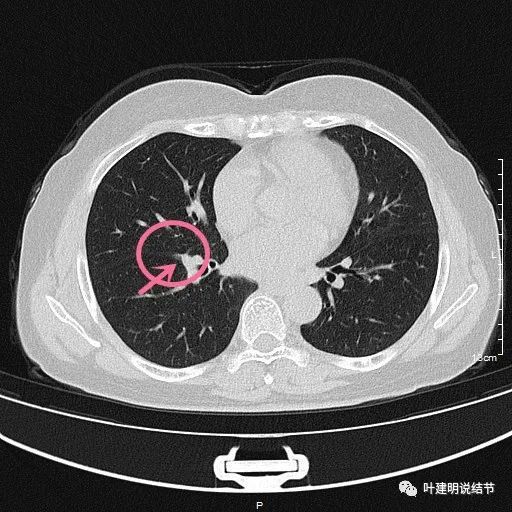

右肺玻璃结节

右肺玻璃结节,

经验积累20211012此消彼长的肺结节会是恶性的吗

19:同为肺磨玻璃结节,一让尽快手术,一让随访不急,玄机在哪?

肺结节读片(18:有些所谓"混杂磨玻璃结节"是假的

体检查出肺多发结节报告示有的是混合磨玻璃结节该赶紧手术吗

中叶另有一次病灶,纯磨玻璃结节,目前甚小,考虑不典型增生或原33